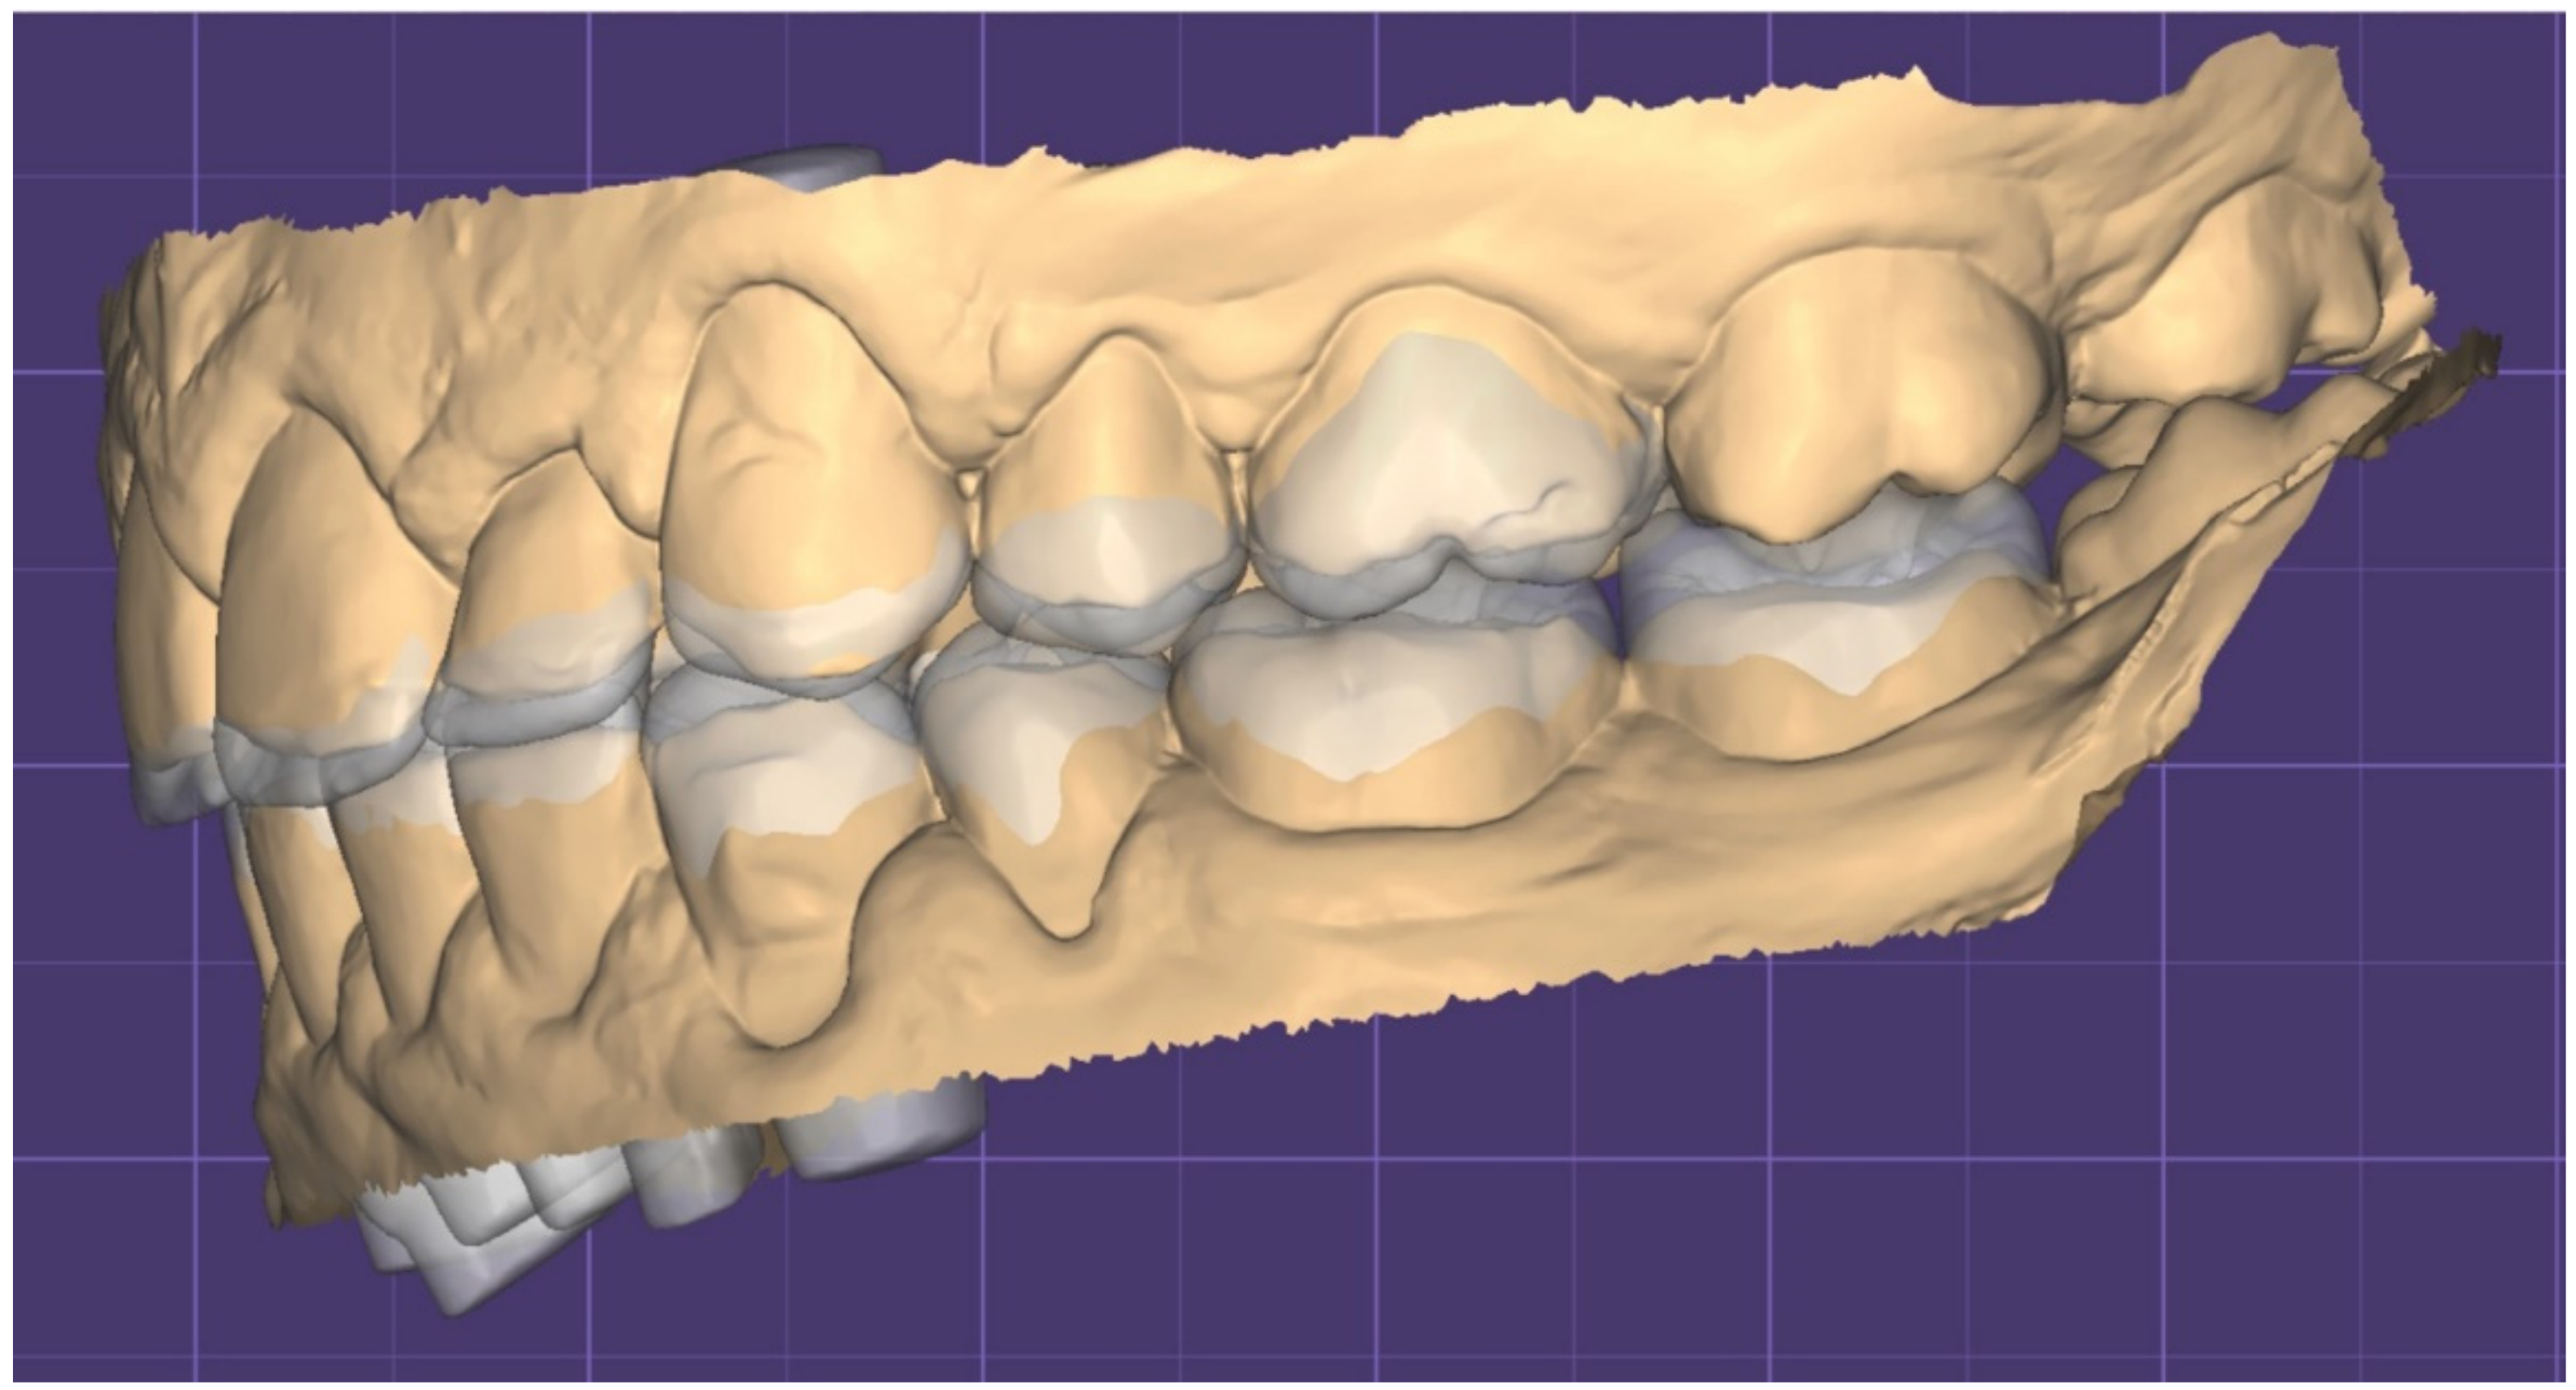

2. Clinical Report

2.1. Planning Phase

2.2. Restorative Phase